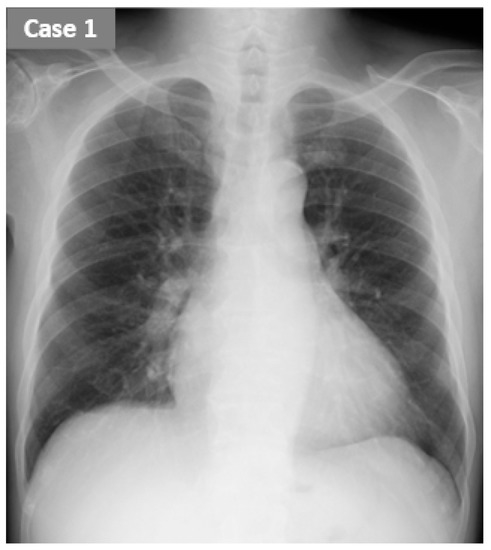

2.1. CASE 1 (ReDS Change from 32 to 30%)